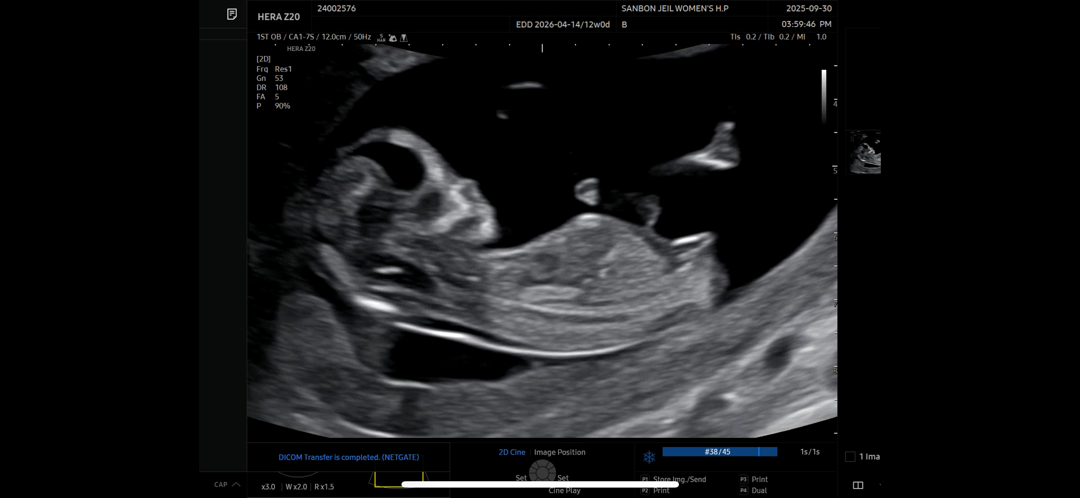

12주5일차!!!! 각도법 부탁드려요!!

어떻게 보이실까요오~~?🥹❤️